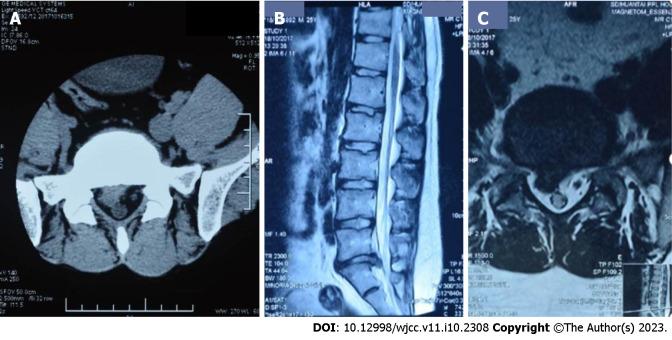

Computed tomography and magnetic resonance imaging (MRI) of the lumbar region of a 25-year-old male diagnosed with LIDH showed prolapse of the L5/S2 disc. The disc extended 1.0 cm beyond the vertebral edge and hung along the posterior vertebral edge. The patient elected a conservative treatment regimen that included traditional Chinese medicine (TCM), acupuncture, and massage. During a follow-up period of more than 12 mo, good improvement in pain was reported without complications. MRI of the lumbar region after 12 mo showed obvious reabsorption of the herniation.

一名25岁男性被诊断为LIDH,其腰椎的计算机断层扫描和磁共振成像(MRI)显示L5/S2椎间盘脱垂。椎间盘超出椎体边缘1.0厘米,并沿椎体后缘悬垂。患者选择了包括中药(TCM)、针灸和按摩在内的保守治疗方案。在超过12个月的随访期内,报告疼痛有明显改善,且无并发症。12个月后腰椎MRI显示突出明显吸收。